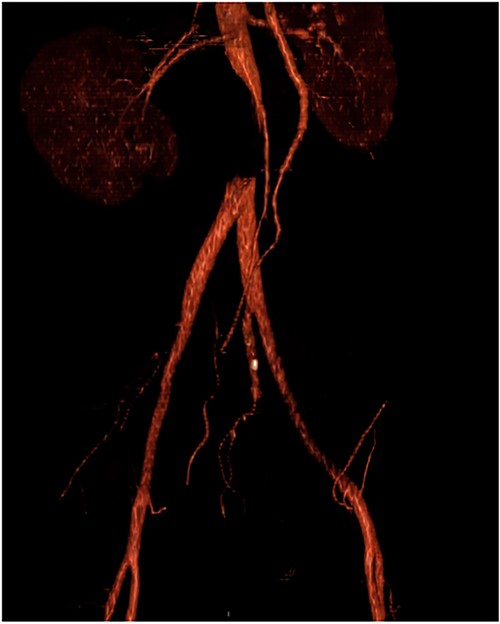

Upon admission to the ED, vital signs were stable, and an arterial duplex revealed diminished flow bilaterally in the common femoral arteries, superficial femoral artery and popliteal arteries, suspicious for aortoiliac disease. A computed tomography angiogram (CTA) with runoff was then conducted, which showed a near-complete occlusion of the infrarenal abdominal aorta below the level of the inferior mesenteric artery (Figs 1 and 2). The patient was promptly seen by vascular surgery and planned for an open aortic thrombectomy.

CTA with occlusion of the infrarenal abdominal aorta above the bifurcation of the iliac arteries.